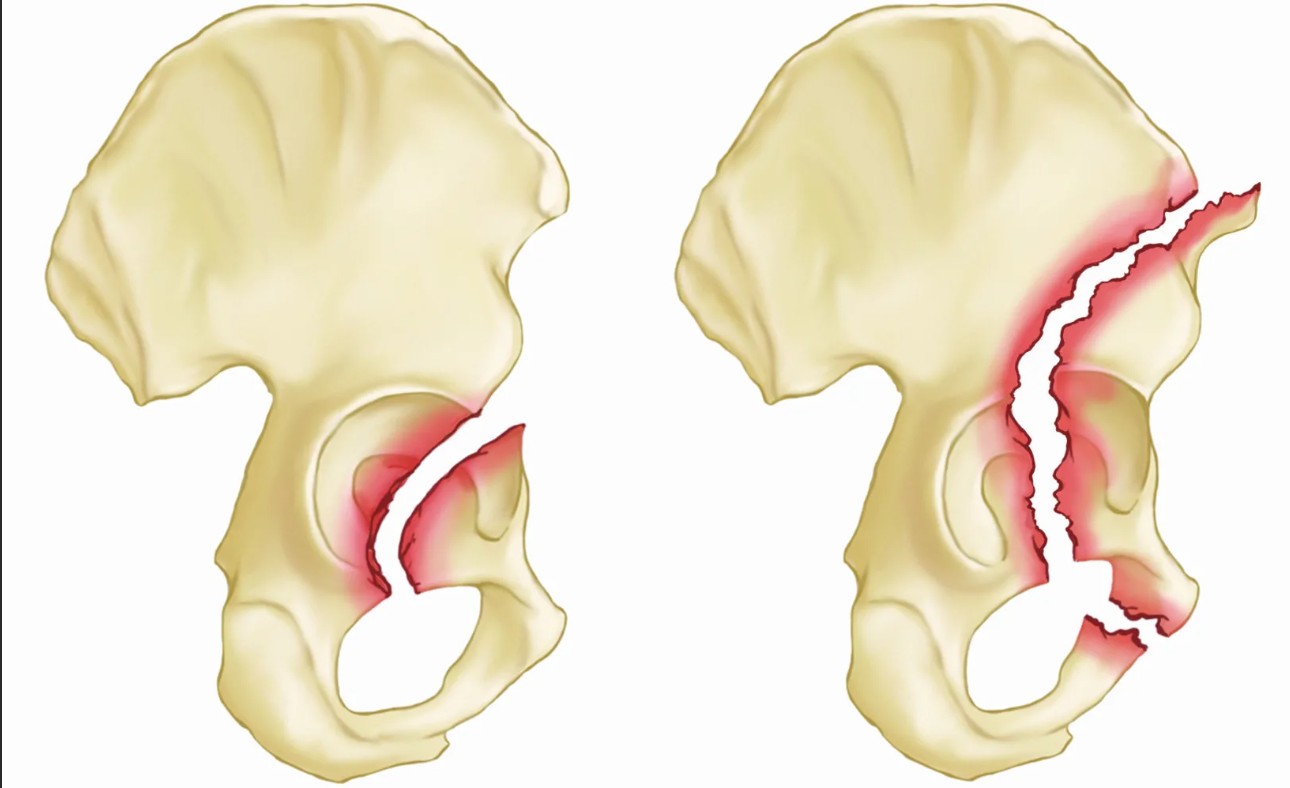

В каждом конкретном случае тревожные симптомы и их интенсивность проявляются по-разному в зависимости от типа травмы. Так, повреждение может быть стабильным, когда поражается лишь кость. Или же оно может быть нестабильным со сдвигами костных отломков, поражением сосудов, нервов, внутренних органов и прочим.

При стабильном повреждении отмечается слабовыраженная боль в области нижней части туловища, а также припухлость в мягких тканях, при прикосновении к которым отмечаются болевые ощущения. А вот при нестабильном переломе можно заметить следующие симптомы:

- Острый болевой синдром, отдающий в пах и поясницу.

- Подкожное кровоизлияние.

- Онемение кожных покровов в области таза.

- Парез и паралич нижних конечностей.

- Недержание мочи.

- Ноющая боль в области брюшной полости.